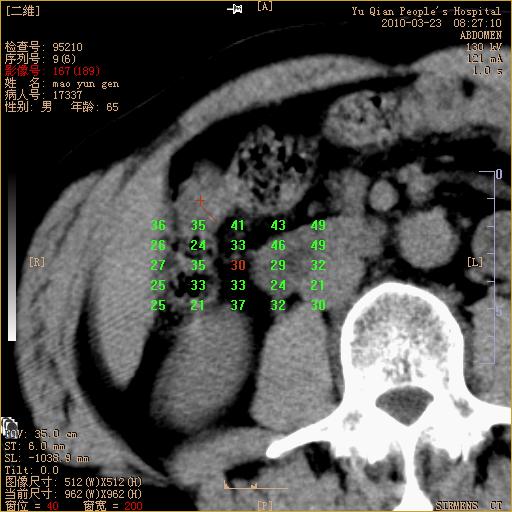

标题: CT25266:消瘦月余,前来肝部检查,请看看肠腔 [打印本页]

标题: CT25266:消瘦月余,前来肝部检查,请看看肠腔

肝区结肠占位,腺癌可考虑,建议肠镜活检。

升结肠肠壁增厚,不均强化,考虑升结肠腺癌可能性,建议肠镜检查。

1)考虑升结肠癌。2)右肾小囊肿。